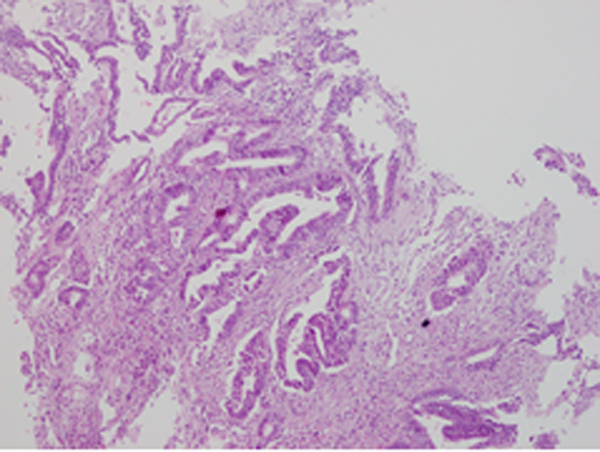

| Hình ảnh theo dõi ung thư trực tràng của bệnh nhân đến nội soi đại trực tràng vừa được phát hiện tại BVĐK MEDLATEC ngày 10/11 vừa qua. |

| Kết quả giải phẫu bệnh sau bấm sinh thiết, kết luận ung thư biểu mô tuyến biệt hóa của bệnh nhân nội soi đại trực tràng thấy có bất thường đến khám tại MEDLATEC ngày 10/11. |